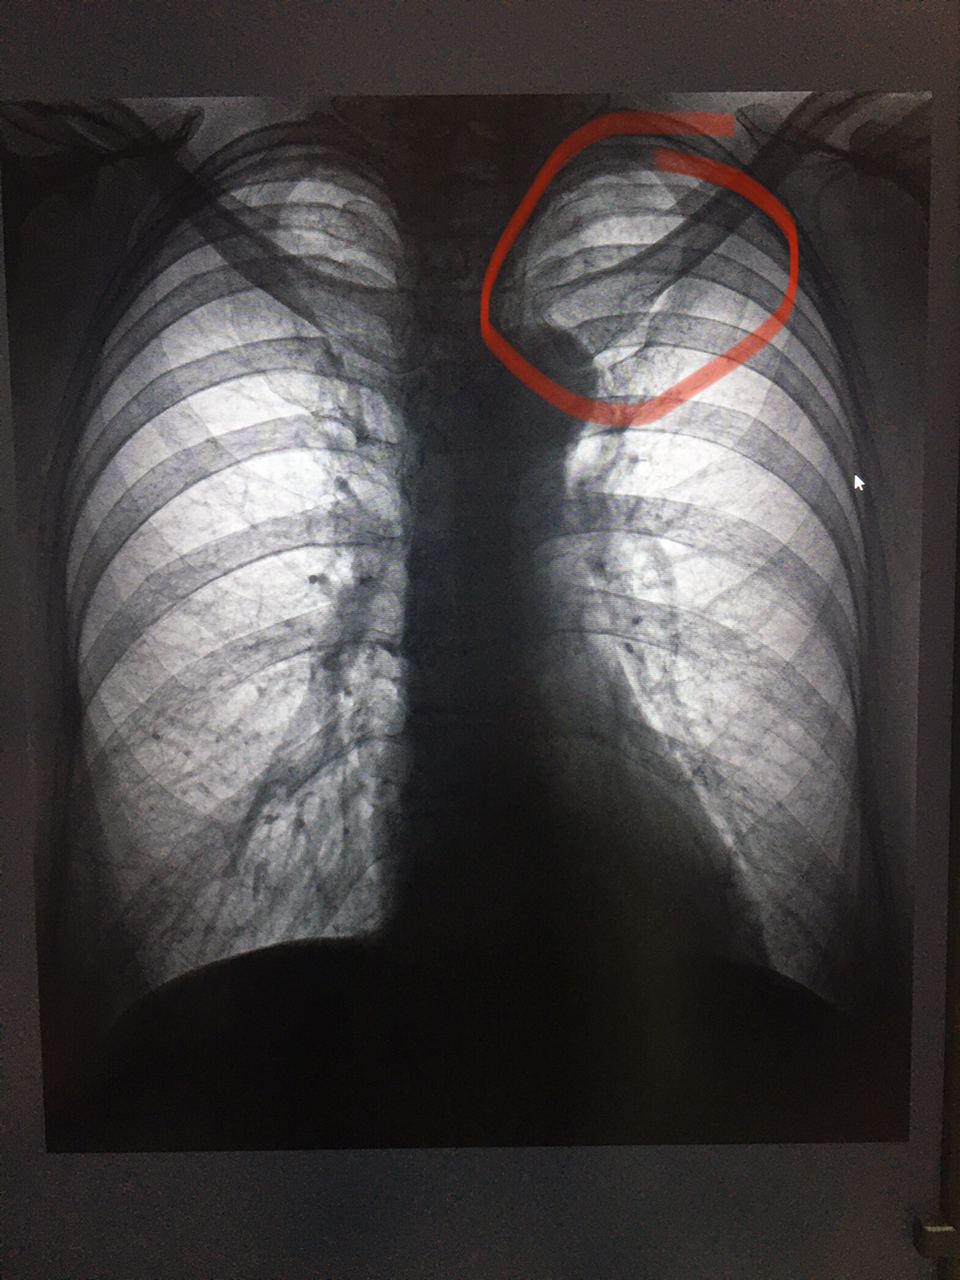

Коллеги, подскажите пожалуйста, есть ли здесь изменения в верхушке слева? Женщина, 1958 г, в направлении Хр. Бронхит?

источник

Спиной надо